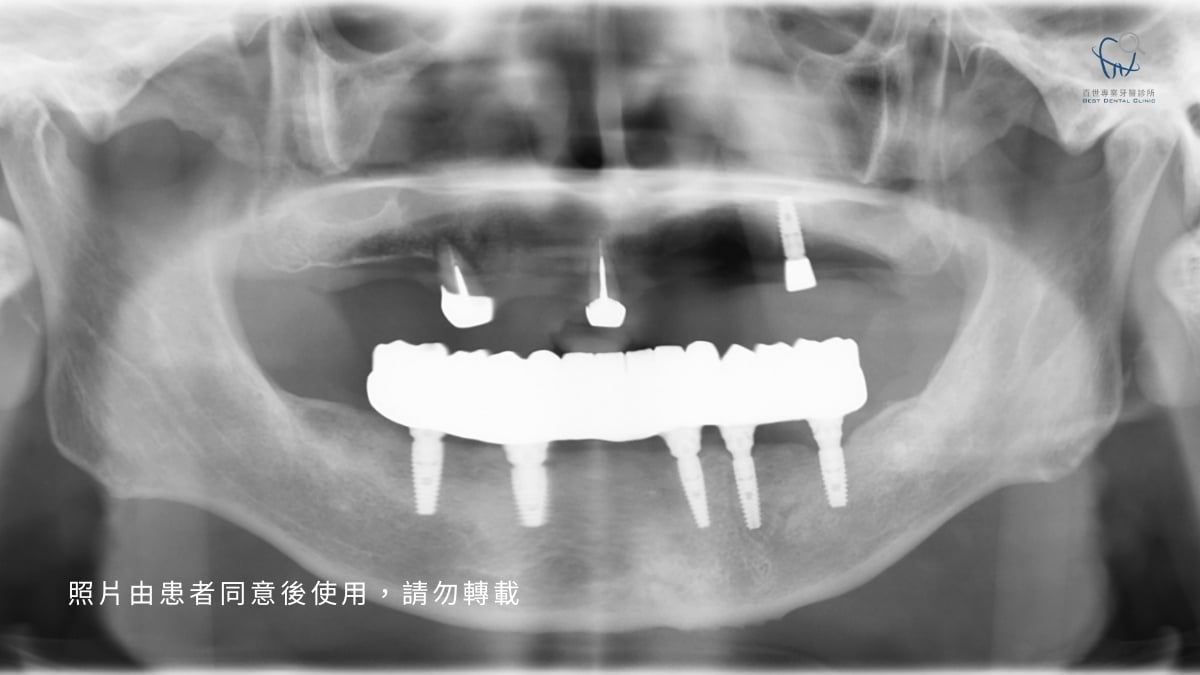

為了解決「磨壞磁鐵」的問題,治標更要治本。我們決定將治療計畫升級為 All-on-5 全口重建固定假牙,在後牙區追加兩支植體,來增加假牙的穩定性:

- 結構強化: 為了穩定植體,我們利用「鈦金屬支架」當骨架,將五支植體一起固定。受力平均的植體能大幅延長使用的壽命。

- 螺絲固位設計: All-on-5 改用螺絲將假牙直接「鎖」在植體上,像把家具釘在牆上一樣穩如泰山,徹底解決鬆動問題。且採可拆卸式設計,未來維修或深度清潔,醫師都能輕鬆卸下保養。